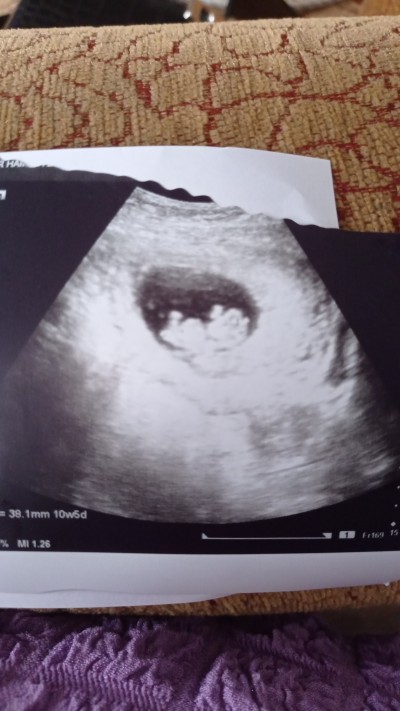

3 Ocak 2022 Hamilelik Dönemi Genel kategorisinde (54 puan) sordu

Merhaba anneler 10+5 tahminnn

Gebelik haftası 11+2